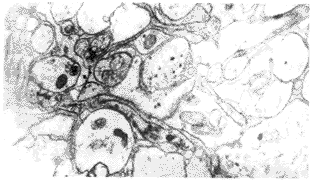

2.2 STC组患者结肠肌间神经丛 与对照组相比,14例STC患者结肠肌间神经丛的超微结构均有明显的病理改变,主要表现在以下两个方面:①神经元及其突起有十分明显的退行性改变,轴突与树突空化呈网格状结构,胶质内出现大小不等的空泡(图1)及脂褐素(图2)等;②轴突末端膨体及突触前区内突触小泡含量明显减少,大部分突触小泡出现空化(图3).

图1 STC组,结肠肌间神经丛明显退行性变,轴突及树突空化呈网格状结构 ×10000